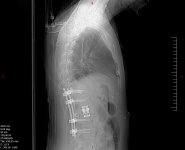

I broke my spine, had two surgeries (T12 arthrodesis), had to relearn how to walk again because I couldn't move my legs after the crash...

I still have a slight paralysis of the left foot (I can't lift up my foot) and above all neuropathic pains 24/24.